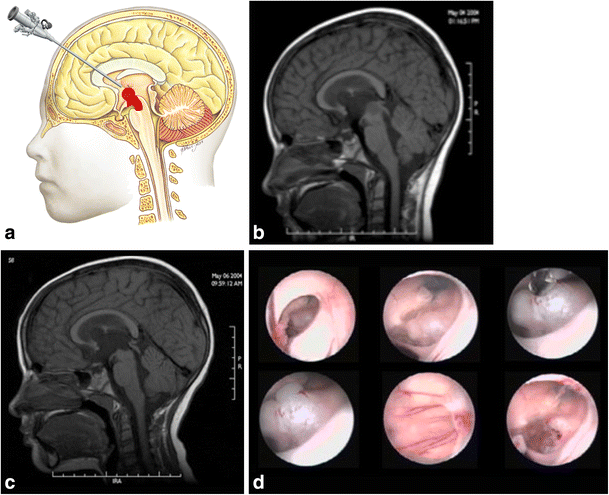

Tumors in the anterior portion of the midbrain usually grow in two directions: toward the third ventricle and toward the interpeduncular cistern. For tumors growing into the third ventricle, an interfornicial, transcallosal, transchoroidal, or transforaminal approach is used. When the lesion is less than 2 cm in size, a neuroendoscope coupled to an ultrasonic aspirator can be used for removal of the tumor, most of which are low-grade astrocytomas (Fig. 3). When these tumors grow toward the interpeduncular cistern, they usually present with Weber syndrome (third cranial nerve impairment and contralateral hemiparesis) (Fig. 4).

Fig. 3

figure 3

a Endoscopic access to tumors located in the anterior and superior portion of the midbrain. b An 8-year-old patient with intracranial hypertension. A lesion is present in the anterior and superior topography of the midbrain. c 3-year follow-up after complete removal of the lesion by endoscopy, with patency of the cerebral aqueduct. Diagnosis was low-grade astrocytoma. d. Intraoperative endoscopic view of the exophytic tumor in the midbrain and after complete resection. After passing through the foramen of Monro, the lesion was seen and removed at the floor of the third ventricle